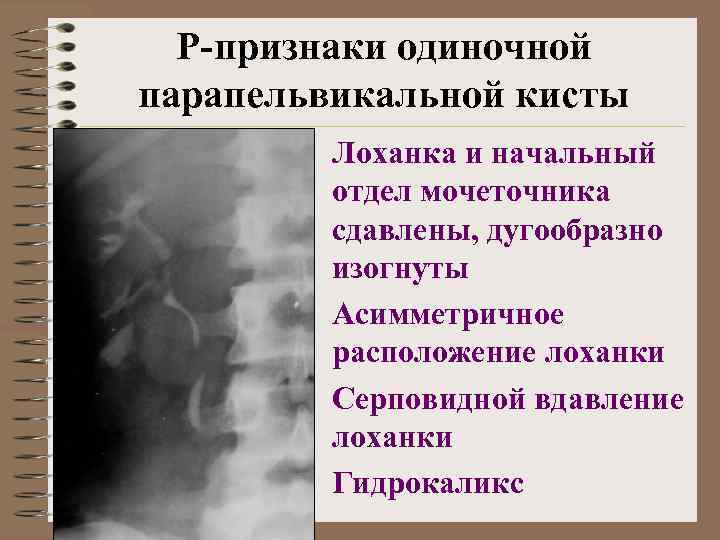

Парапельвикальные кисты • 3% врожденных кист почек • Причина – внутриутробное воспаление • Морфологически – резко расширенный лимфатический сосуд с признаками воспаления и облитерации просвета (ретенционная лимфатическая киста) • Нарушение пассажа мочи редко • Одиночная, множественная • Дифференцировать с гидронефрозом

Р-признаки одиночной парапельвикальной кисты • Лоханка и начальный отдел мочеточника сдавлены, дугообразно изогнуты • Асимметричное расположение лоханки • Серповидной вдавление лоханки • Гидрокаликс